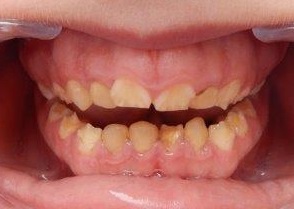

Photographie intrabuccale